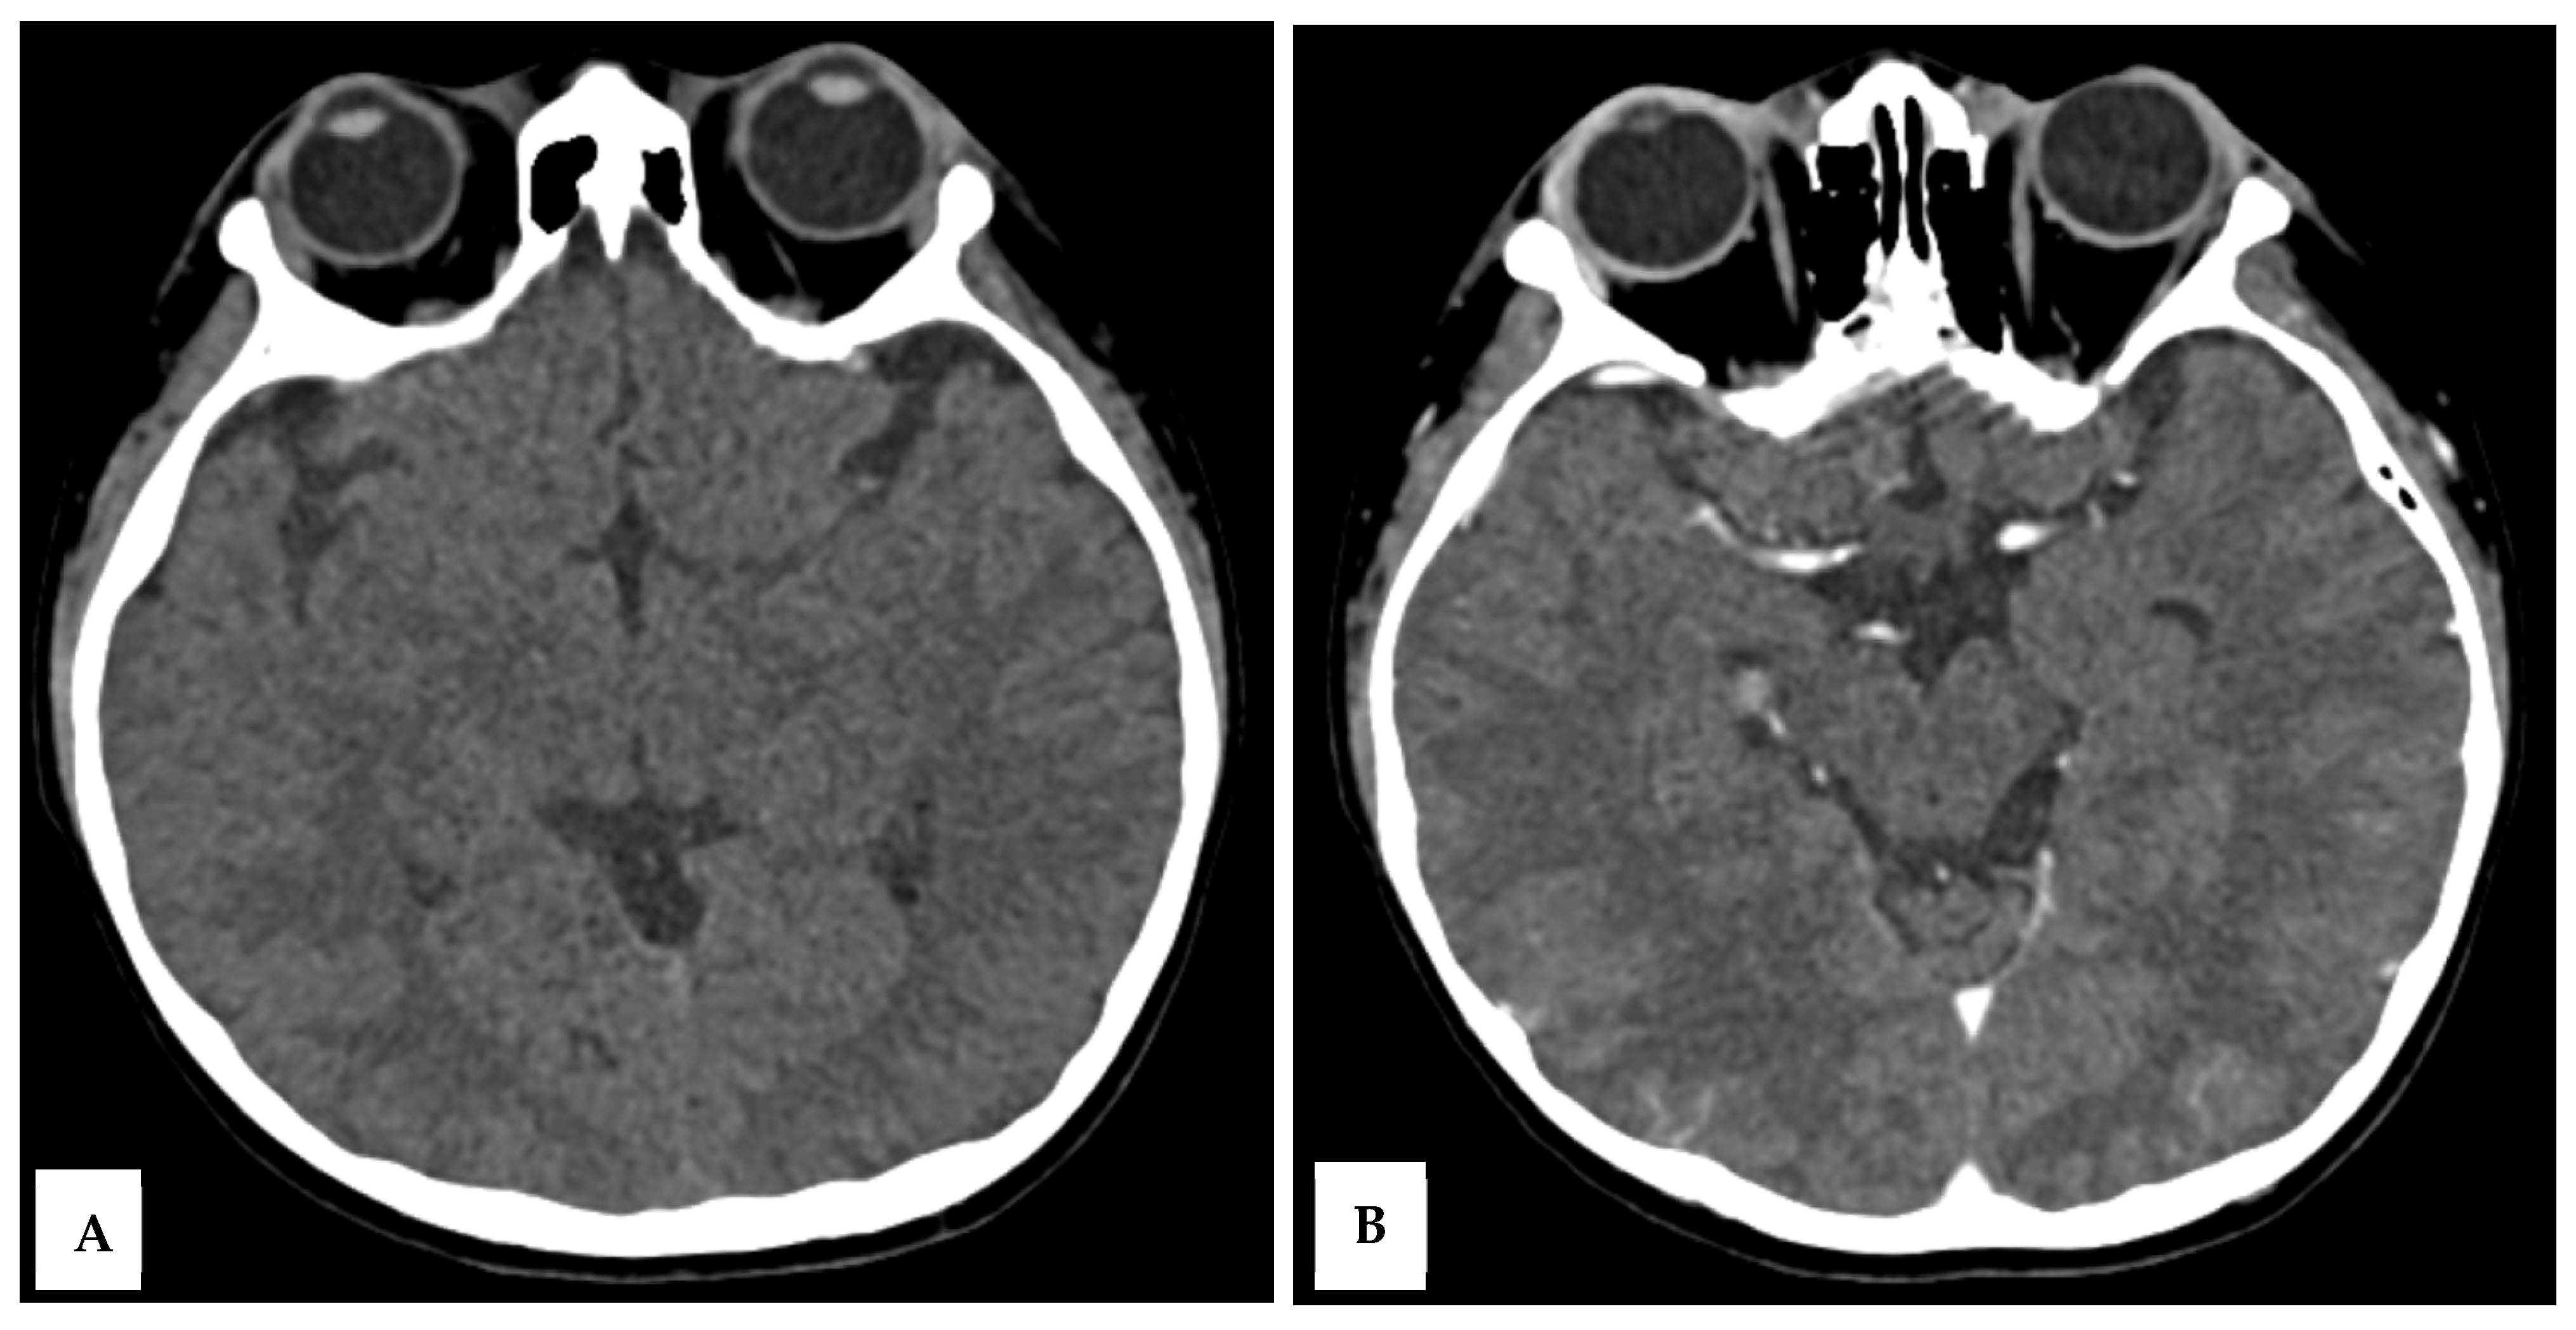

On day 9, the patient’s GCS improved to E4M6V5, with the resolution of fever and seizures. However, he developed sudden blurry vision, headache, and vomiting, without clinical seizures. Ophthalmological examination revealed normal funduscopy but significantly reduced visual acuity (1/300 bilaterally). His blood pressure was elevated to 147/89 mmHg, HR 145 bpm, RR 22 breaths/min, and temperature 37.9 °C. Brain MRI was performed on a 1.5T GE Healthcare scanner with multiplanar T1-weighted imaging (T1WI), T2WI, fluid attenuation inversion recovery (FLAIR), diffusion weighted imaging—apparent diffusion coefficient (DWI-ADC), susceptibility weighted imaging (SWI), with T1 fat saturated (T1FS) pre- and post-contrast. MRI revealed hyperintense lesions in the cortical and subcortical regions of the bilateral parieto-occipital lobes, posterior temporal lobes, left precuneus, bilateral central sulcus areas, and cerebellar periphery, consistent with posterior reversible encephalopathy syndrome (PRES) (Figure 2A–E). There was no contrast enhancement or hemosiderin deposition on SWI.

Figure 2. A 10-year-old boy presented with visual disturbance and seizures. (A,B) Axial T2 dark-fluid images show hyperintense lesions involving the cortical and subcortical regions of the bilateral parieto-occipital lobes, bilateral posterior temporal lobes, left precuneus gyrus, bilateral central sulcus areas, and peripheral cerebellar hemispheres (arrows). (C) Sagittal T2-weighted image confirms the posterior predominance of the lesions. (D) Diffusion-weighted image shows no diffusion restriction. (E) The apparent diffusion coefficient map demonstrates corresponding hyperintensities, consistent with a vasogenic edematous process.

This case highlights that PRES is associated with reversible neurological complications in MIS-C. The temporal sequence, systemic inflammation, transient hypertension, seizures, and visual loss match the classic presentation of PRES [1,2]. MRI confirmed bilateral parieto-occipital and posterior temporal cortical–subcortical hyperintensities, consistent with vasogenic edema rather than cytotoxic injury. The normal CT findings emphasize the superior sensitivity of MRI in detecting PRES [5].

The proposed mechanism involves immune-mediated endothelial dysfunction triggered by cytokine release in MIS-C, leading to cerebral autoregulatory failure and increased vascular permeability [2,6]. Several immunology panels, such as immunoglobulins, were raised in MIS-C patients, raising the possibility of autoimmune components [7]. Unfortunately, due to resource constraints at that time, these panels could not be checked in our patient. The child’s mild hypertension likely compounded the process, causing reversible blood–brain barrier disruption. The absence of diffusion restriction and the presence of high ADC values supported a vasogenic pattern, correlating with the complete clinical recovery.